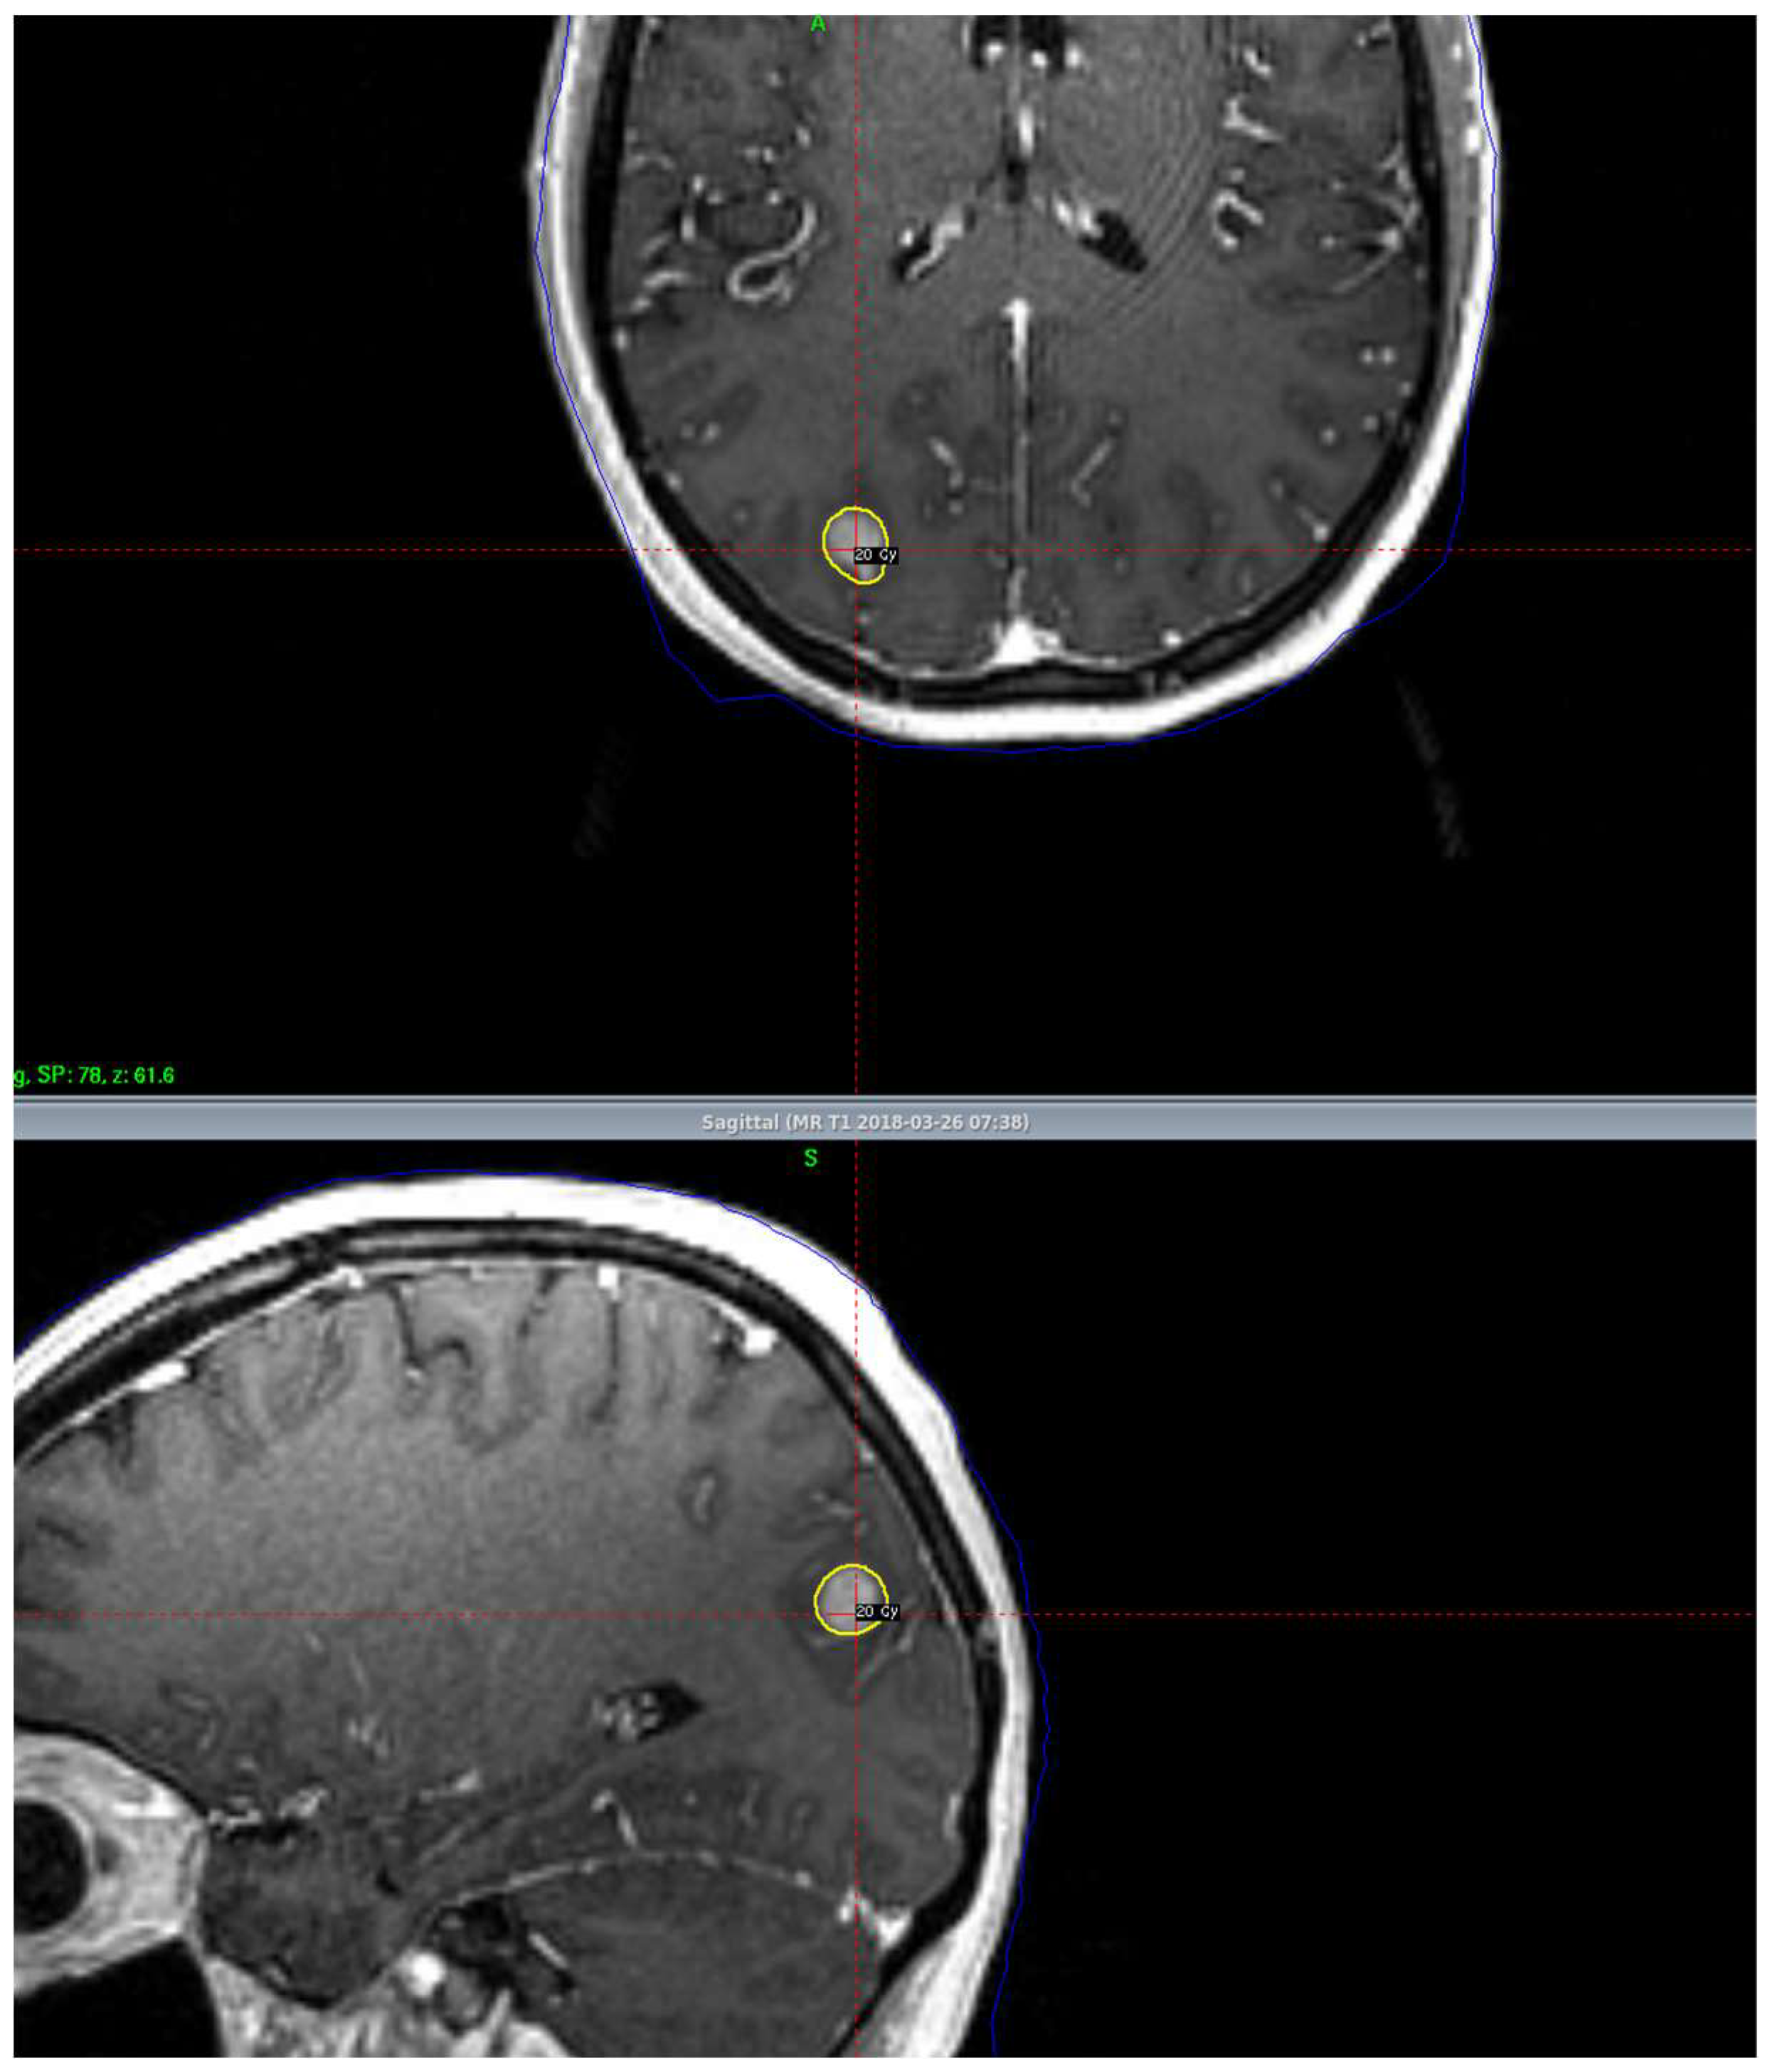

3. Stereotactic Radiosurgery